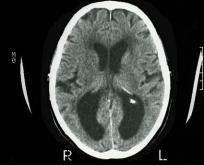

Légende

Dans le cas des neurones sains (en haut), la protéine Tau est normale. Dans le cas de neurones malades (en bas), des amas de protéines Tau anormales …